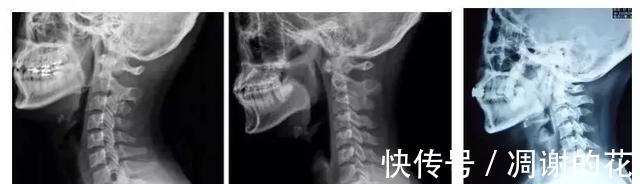

颈椎病治疗,除了上医院、吃药,在家时还可以利用矿泉水瓶做些简单的保护颈椎方法。养护:大部分患者都会有颈椎生理曲度变直或者反弓,这都是低头惹的祸。